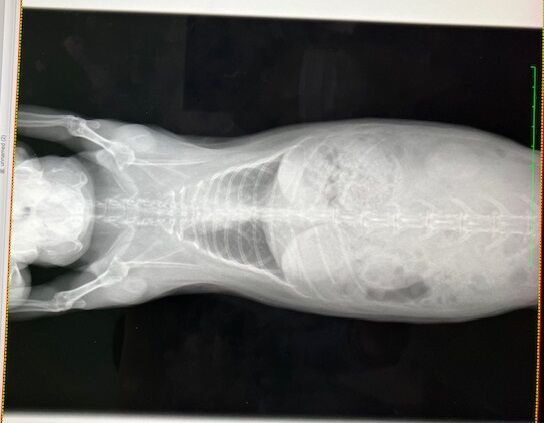

レントゲンでは...

歯根の問題はなさそうですが、鼻の奥の方(?)

堆積物か何か、何かがあるかもしれない、みたいな話でした。

どこかすぐ忘れるから指さし撮影(^_^;)

鼻涙管の通り道ではないので、排除となると外部から穴をあけるらしい…。

詳細はCTなどを用いて調べられる。

まあ、強いていえば、という感じでしたし、ひとまず経過観察です。

胸の方は

こちらも大きな問題なさそう、ですが、

心臓の輪郭がはっきりしてない箇所があります。

(向かって右上、白くモヤってるところ)

こちらは、ちょうど3年前、

去勢手術の術前検査で撮影したレントゲンがあったので比較すると、

ほとんど変化がありません。

肺の一部が弱ってる(しぼんでる?)のかなと。

(うさぎは肺が6個やったっけか?

1つ2つ機能しなくなっても生活に支障はない、とか…

過去の記憶ですが💦)

また、生まれつき(先天性)かも。

※緊急性の高い呼吸困難の症状が出ていない場合での見解です※

(向かって左が現在)

なので、リンパ腫などの可能性は低く、肺の一部が弱ってる(しぼんでる?)のかなと。